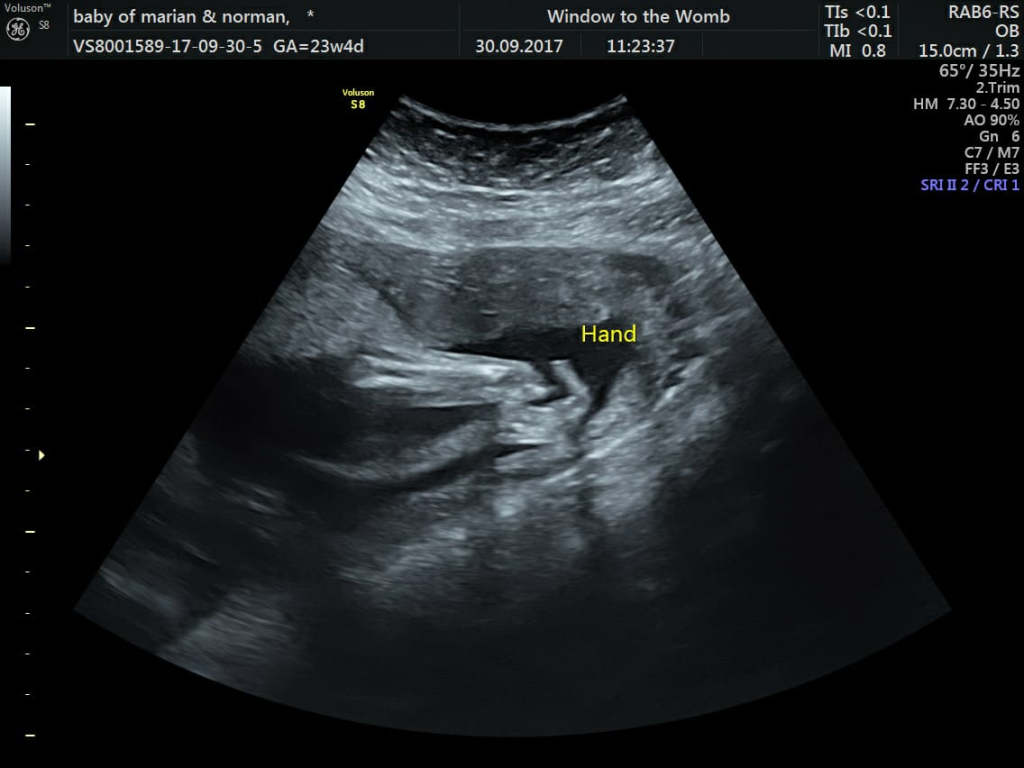

Parents Marian and Norman attended their 20-week scan at the hospital to unsuspectingly find concerns with baby Jacks’ heart. After returning for another scan at 23 weeks, they couldn’t get the view of Jacks’ heart they needed…but discovered an absent left hand. Marian had planned to visit us at Window to the Womb for a scan at 28 weeks, but after discovering the possible heart issues, decided they needed reassurance as soon as possible. They joined us 3 days later, mainly to see if baby was okay through our technology.

Baby Jacks’ 4D Scan at 23 Weeks

Marian got in touch recently and gave us the wonderful news…the heart consultant had given Jack the all clear at 28 weeks! He was born happy and healthy on the 17th January, weighing 7lbs 4 oz. Although his left hand is absent, he is missing less than expected with more of a wrist; this means he will have more support.